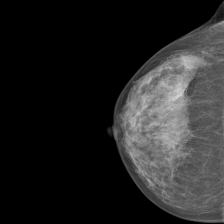

Despite significant progress in biomedical AI, most models today are unimodal single task systems [1, 2, 3]. Consider an existing AI system for interpreting mammograms [4]. Although the system obtains state-of-the-art (SOTA) performance on breast cancer screening, it cannot incorporate relevant information such as patient health records (e.g., breast cancer gene screening status), other modalities such as MRI, or published medical literature that might help contextualize, refine, and improve performance. Further, the system’s output is constrained to a pre-specified set of possible classifications. It cannot verbally explain its prediction or engage in a collaborative dialogue to learn from a physician’s feedback. This bounds performance and utility of these narrow, single-task, unimodal, specialist AI systems in real-world applications.

| Mammography | VinDr-Mammo |

|

| Mammography | VinDr-Mammo | Macro-AUC | 64.50% [49] | 51.49% | 71.76% | |||||

| Macro-F1 | N/A | 16.06% | 35.70% | |||||||

| CBIS-DDSM (mass) | Macro-AUC | N/A | 47.75% | 73.31% | ||||||

| Macro-F1 | N/A | 7.77% | 51.12% | |||||||

| CBIS-DDSM (calcification) | Macro-AUC | N/A | 40.67% | 82.22% | ||||||

| Macro-F1 | 70.71% [70] | 11.37% | 67.86% | |||||||

Multimodal tasks bottlenecked by vision encoder performance For tasks such as mammography or dermatology image classification, where nuanced visual understanding is required but minimal language reasoning is needed (outputs are classification label tokens only), the performance improved from Med-PaLM M 12B to Med-PaLM 84B but plateaued for the 562B model, possibly because the vision encoder is not further scaled in that step (both the Med-PaLM M 84B and 562B models use the same 22B ViT as the vision encoder), thereby acting as a bottleneck to observing a scaling benefit. We note the possibility of additional confounders here such as the input image resolution.